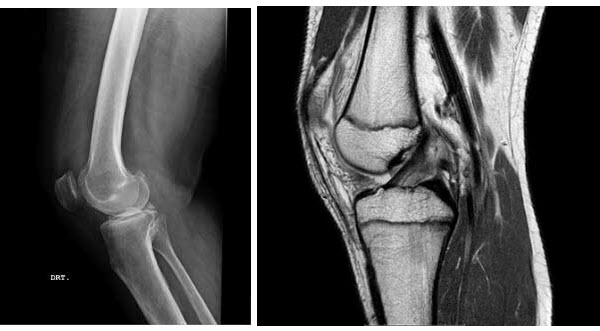

A artrose de joelho é uma das doenças reumáticas mais frequentes e incapacitantes, especialmente após os 50 anos. Trata-se de um processo degenerativo que compromete